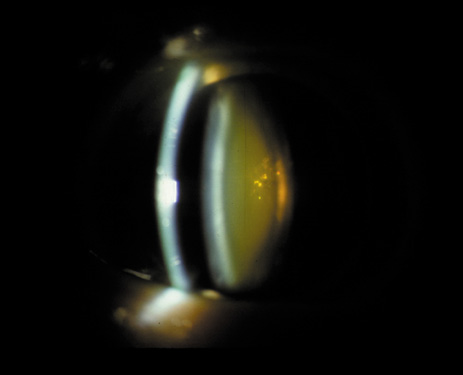

Nuclear cataracts tend to progress slowly. The refractive index of the lens changes as the nucleus progressively hardens, which usually results in increasing myopia.20,21 In some patients this is accompanied by optical distortion, especially of distant images, while near vision remains unaffected. A nuclear cataract is best seen with the narrow-beam direct illumination employed by the slit-lamp, which reveals the color and generalized haze or opalescence of the nucleus. In the early stages, the two halves (cotyledons) of the embryonic nucleus remain visible (Fig. 3). Later the entire nucleus appears as a homogeneous mass in contrast to the cortex (Fig. 4). Retroillumination may show the “oil droplet” effect (Fig. 5). Sometimes one may notice crystals in the lens nucleus (known as a Christmas tree cataract; Fig. 6A and B).

Fig. 6. Slit-lamp appearance of a Christmas tree cataract, showing crystals in the nucleus.